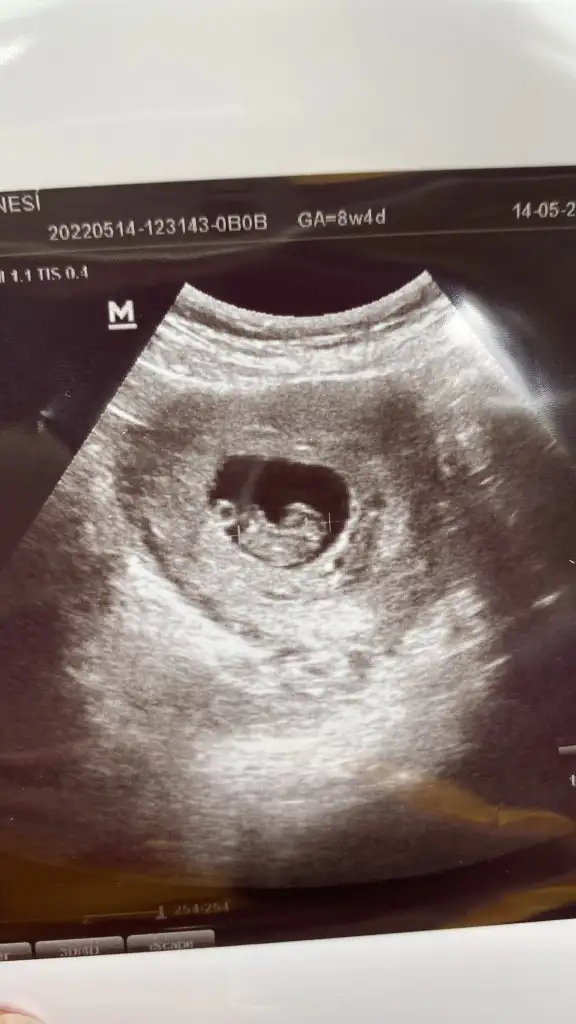

8 haftalık burda güzel teyzeleri çok merak ediyorum bana da yorum yapın annem 3 sene tüp bebek deneyip bana hamile kaldı şimdi cinsiyetimi öğrenip hasırlık yapmak istiyorSelam Kızlarbir çok kişi gruplardan beni bilir. Yine yetiştim imdatlara

5 ve 14. haftaya kadar olan ultrason fotolarınızı paylaşın. Vajinadan mı yoksa karından mı çekildiğini ve kaç haftalık olduğunu da mutlaka belirtin.